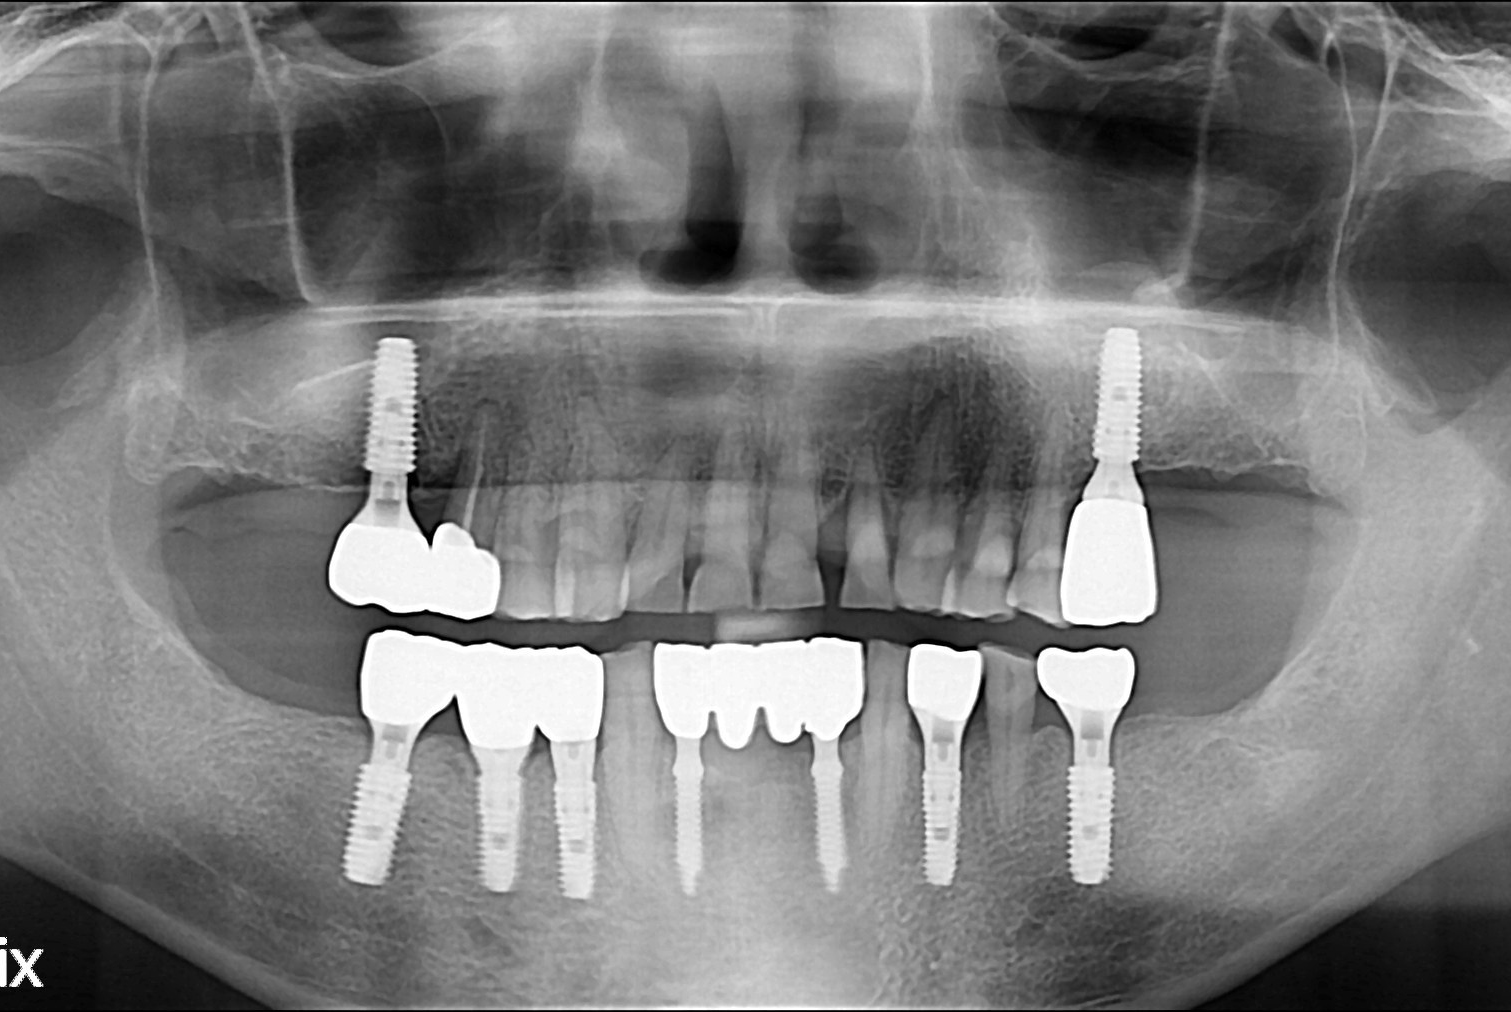

[임플란트] 임플란트

치료전 : 2017-05-11

세종치과는 많은 환자와 다양한 케이스를 바탕으로 항상 편안한 임플란트 수술을 제공하고자 노력하고,

오래동안 튼튼히 쓸 수 있는 임플란트 수술을 가장 큰 목표로 삼고 있습니다